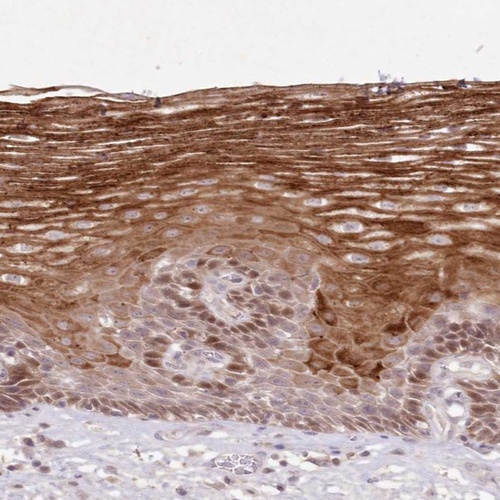

Immunohistochemical staining of human esophagus shows strong cytoplasmic positivity in squamous epithelial cells.